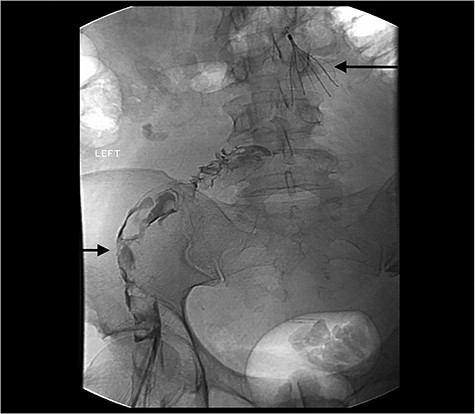

After the case was discussed with multiple teams and deemed too unsafe for surgery, the patient was admitted to the intensive care unit, bilateral thrombolytic catheters were placed from the legs to above the IVC, and he was treated with intravascular thrombolytic (Alteplase and Heparin) therapy (Fig. 3). On Day 5, he developed bloody emesis and was noted to have a hemoglobin drop from 12 to 8 g despite blood transfusions. The patient was resuscitated, and an EGD demonstrated a blackened esophagus of the entire esophagus with no involvement into the stomach (Fig. 4). Considering these findings, transthoracic echocardiogram (TTE) and chest computed tomography (CT) angiogram (CTA) were performed, which revealed patent foramen ovale (PFO) with small right to left shunt and an edematous esophagus and duodenum with no perforation or arterial inflow problem, respectively. No intervention was performed. The patient eventually stabilized and a repeat EGD a week later showed resolution of the ischemic esophagus. Patient was started back on liquid diet, which was advanced to solid diet and was discharged a week later.

IVC filter and bilateral intravascular catheters to administer thrombolytic (Alteplase and Heparin) therapy. The upper left corner shows the Thrombolytic Catheter and the right lower arrow shows that IVC filter.